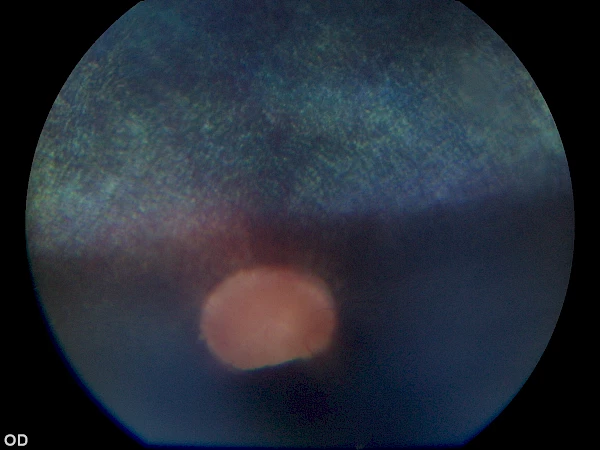

Limbales Melanom vor Operation Limbales Melanom vor Operation

nach Operation nach Operation

1 Jahr nach Operation 1 Jahr nach Operation